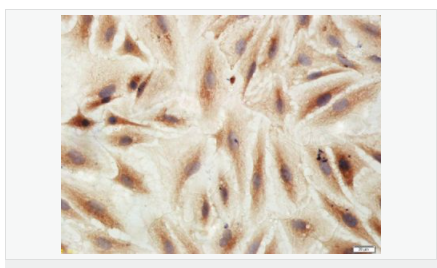

| 產(chǎn)品應(yīng)用 | WB=1:500-2000 IHC-P=1:100-500 IHC-F=1:100-500 Flow-Cyt=3ug/test ICC=1:100-500 IF=1:100-500 (石蠟切片需做抗原修復(fù)) not yet tested in other applications. optimal dilutions/concentrations should be determined by the end user. |